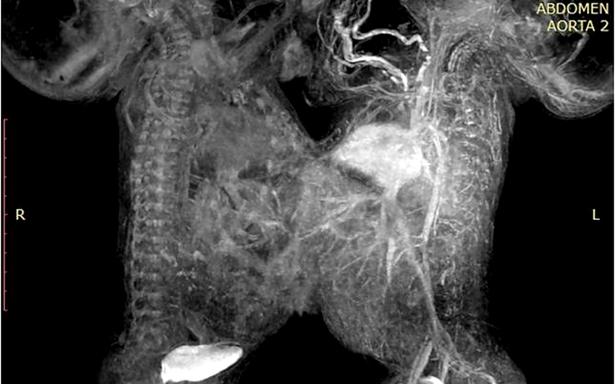

Tras diversos exámenes de tomografía, ecocardiograma y resonancia magnética, cuando los niños cumplieron 41 días de vida, fueron programados para la cirugía que los separaría.

El equipo multidisciplinario de cirujanos, anestesistas y enfermería, dio inicio a la operación a las 9:00 horas; de manera cuidadosa realizaron la incisión en la línea media que unía a los gemelos y mediante la técnica de electrocoagulación, lograron separarlos a las 12:43 horas, sin que se presentaran complicaciones.

Los especialistas requirieron un par de horas más para finalizar la intervención quirúrgica, en la que se aseguraron de que los bebés mantuvieran con buen funcionamiento todos sus órganos.